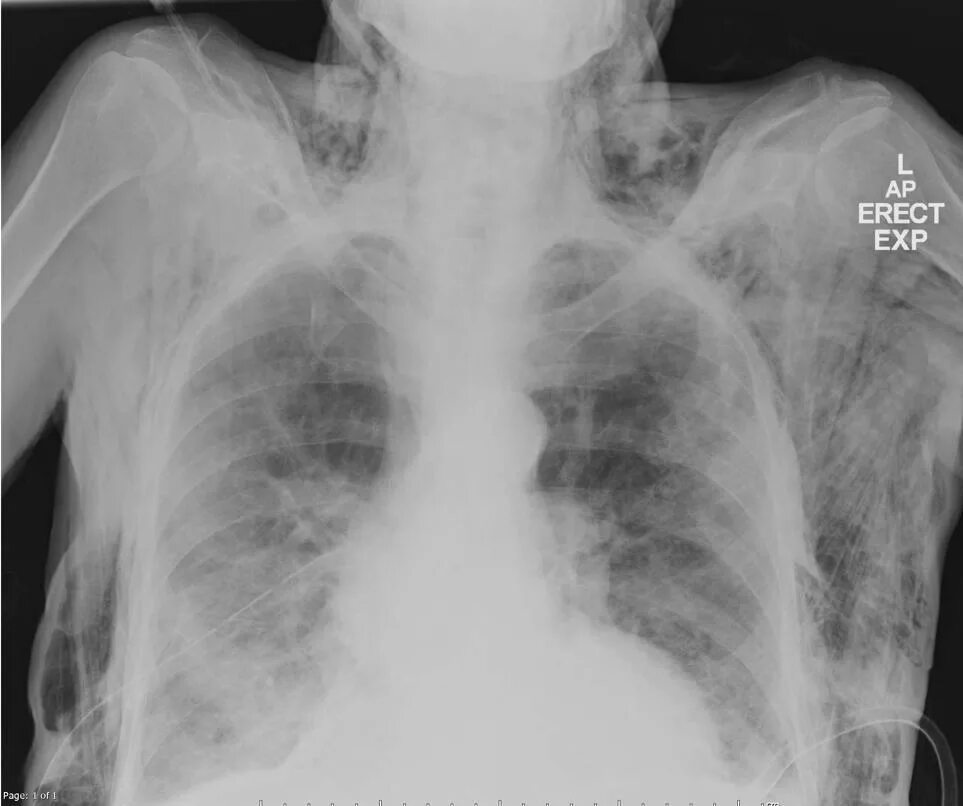

Эмфизема мягких